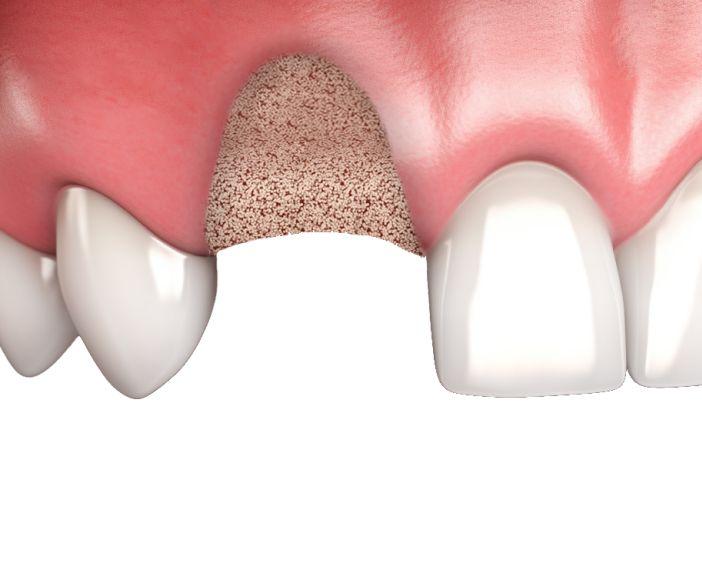

Синус-лифтинг — процедура по увеличению объёма костной ткани. Она необходима из-за особенностей анатомии: корни 5, 6 и 7 зубов верхней челюсти расположены очень близко к верхнечелючстным синусам, а иногда частично входят в их полость. Гайморовы пазухи (или синусы) — это крупные воздухоносные пространства на верхней челюсти по обе стороны от носа, относящиеся к дыхательной системе. Их объём может быть настолько большим, что необходимость в синус-лифтинге возникает даже при имплантации в зоне 3–4 зубов. Оценить размер синусов и высоту костной ткани позволяет компьютерная томография — её можно пройти прямо в нашей клинике. Благодаря синус-лифтингу создаётся прочное основание для импланта, что обеспечивает его долгосрочную стабильность. Процедура проводится под местной анестезией или седацией, а современные материалы гарантируют быструю регенерацию кости. Уже через несколько месяцев в области синус-лифтинга формируется крепкая костная ткань для идеальной приживаемости импланта.

После удаления зубов кость быстро теряет объём. Без синус-лифтинга имплант может не прижиться,или даже повредить пазуху, в случае его установки в верхнюю челюсть.

Основные показания к синус-лифтингу

Кость в боковом отделе челюсти часто бывает истончённой — особенно если зуб удалён давно. Синус-лифтинг восстанавливает необходимый объём.Подходит как при единичном отсутствии зуба, так и при необходимости восстановления всей жевательной группы.

• Синус верхней челюсти расположен слишком низко

Анатомическая особенность, при которой пазуха опускается, а высоты кости становится недостаточно для импланта. Врач поднимает мембрану и формирует устойчивую основу для будущей имплантации.

• Потеря объёма кости после удаления зуба

Чем дольше отсутствует зуб, тем больше уменьшается толщина кости. Синус-лифтинг позволяет восстановить её.